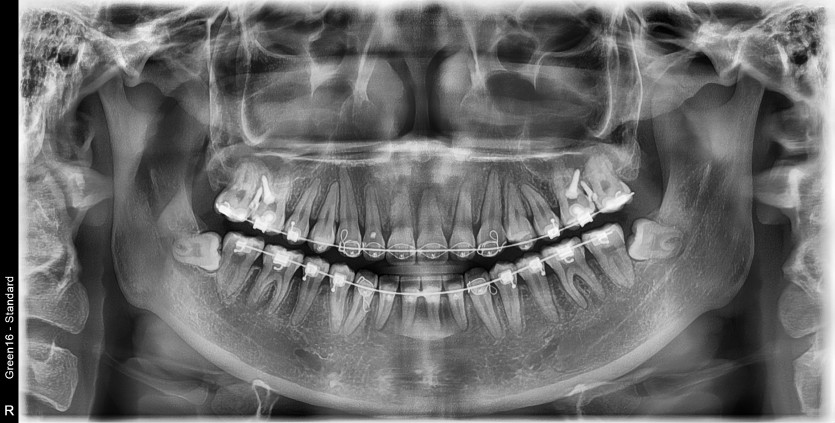

#18 사랑니 발치

구강 외과 전문의가 당일 발치했습니다.